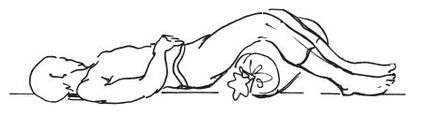

Ако атаката на ишиас сте разбрали, трябва да изчакате малко, а след това бавно и много внимателно да заеме позиция, в която болката е по-леко.

Когато лумбосакралната облекчение ишиас носи седнало положение с подкрепата на ръка.

Трябва да лежи по гръб върху твърда повърхност, малко навеждане и вдигане на крака.